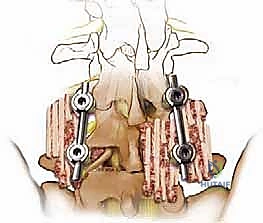

تقنية TLIF (الاندماج الفقري القطني عبر الثقب)

تُعد TLIF تطوراً لتقنية PLIF. بدلاً من الدخول مباشرة من المنتصف وسحب الأعصاب بشكل كبير، يتم الوصول إلى القرص الغضروفي من جانب واحد عبر "الثقبة" (Foramen) - وهي الفتحة التي يخرج منها العصب.

* الميزة: تتطلب سحباً أقل بكثير للأعصاب الشوكية، مما يقلل من خطر الإصابة العصبية ويقلل من تندب الأنسجة، وغالباً ما تتم عبر شقوق جراحية أصغر.

| عدد الأقفاص (Cages) | يتم وضع قفصين (واحد في كل جانب). | يتم وضع قفص واحد كبير مائل. |

الخطوة 4: زراعة القفص والطعم العظمي (Cage Insertion)

يتم إدخال قفص مصنوع من مادة PEEK أو التيتانيوم، مملوء بطعم عظمي (يؤخذ غالباً من المريض نفسه أو طعم صناعي)، في المساحة الفارغة. هذا القفص يعيد الارتفاع الطبيعي للفقرات ويخفف الضغط عن منافذ الأعصاب.